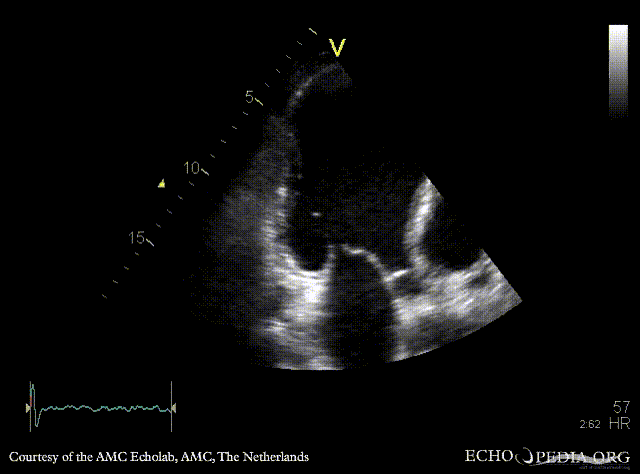

| Courtesy of: AMC Echolab, AMC, The Netherlands | |

| A4CH: apical aneurysm of left ventricle | A2CH: apical aneyrysm of left ventricle |